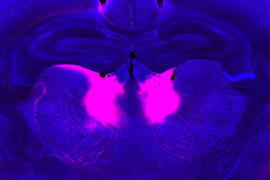

Caption: MIT researchers have identified neurons in the mediodorsal thalamus (labeled pink) whose dysfunction can lead to impairments in the ability to update beliefs based on new information.

MIT researchers have identified neurons in the mediodorsal thalamus (labeled pink) whose dysfunction can lead to impairments in the ability to update beliefs based on new information.

Using functional ultrasound imaging and electrical recordings, the researchers found that the brain region affected most by the grin2a mutation was the mediodorsal thalamus. This part of the brain connects with the prefrontal cortex to form a thalamocortical circuit that is responsible for regulating cognitive functions such as executive control and decision-making.